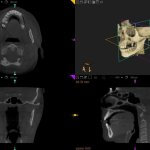

Die 3D Zahntechnik arbeitet dabei hauptsächlich mit dem Cone Beam CT-Verfahren: Das Gerät ist deutlich kleiner und auch preiswerter, als ein herkömmlicher Computertomograph, bei dem der Patient auf einer Liege durch den Untersuchungstunnel (Gantry) gefahren wird. Das Cone Beam CT-Verfahren dagegen arbeitet mit einem mobilen Scanner, der um den Kopf des Patienten herumgeführt wird und ihn mit einem kegelförmigen Röntgenstrahl abtastet. Dabei wird in nur 20-40 Sekunden ein kompletter 3D-Scan des Mundbereichs erstellt, ganze 10 Sekunden genügen, um einen einzelnen ausgewählten Bereich zu erfassen.

Eine 3D CT-Aufnahme besteht aus mehreren hundert 2D-Bildern, die digital übereinandergelegt und zu einem ‚durchfahrbaren‘ 3D-Modell des Schädels zusammengesetzt werden. Sie lässt sowohl Höhe, Dicke und Breite von Kieferknochen und Zähnen erkennen, als auch – wenn auch etwas weniger präzise als die herkömmliche CT – Weichgewebe und Nervenkanäle. Zudem ermöglicht das 3D CT die Messung der Knochendichte.

Durch die 3D-CT-Diagnostik ist es möglich, auch exakte Messungen bezüglich der Knochenbreite und Knochendichte vorzunehmen, in Problemfällen Wölbungen und Knochenhöhlen auf einzelnen Schichtaufnahmen erkennbar zu machen, sowie die Position und den Verlauf der Nervenbahnen zu veranschaulichen. Man erhält eine überlagerungsfreie Darstellung und sieht alles Verborgene, was bei der Planung von implantologischen Eingriffen enorm wichtig ist.

Dr. Gelencsér: Bei der Aufnahme dreht sich das Gerät bis zu 360 Grad um den Patienten. Aus den Daten, die das konische Strahlenbündel liefert, wird ein Datensatz erstellt, der zur Berechnung von Primär- und Sekundärrekonstruktionen dient. Die gewünschten Messungswerte erscheinen dann per Mausklick auf der Aufnahme.